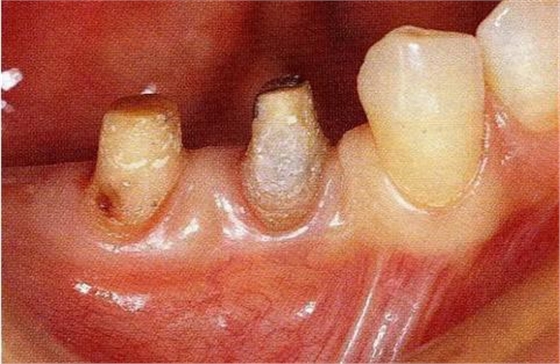

圖18-4▲正畸結(jié)束后6個月,骨外科處理后的狀態(tài)。附著齦嚴(yán)重不足。

圖18-5▲骨外科處理后牙槽骨平坦,同時為了獲取附著齦進(jìn)行游離齦瓣移植。

圖18-6 ▲術(shù)后6個月的狀態(tài),獲得足夠的附著齦。

圖18-7(左),8(右)▲佩戴最終修復(fù)體的口腔內(nèi)照片和X線片,牙槽骨平坦化,牙周袋探診2mm以內(nèi)。